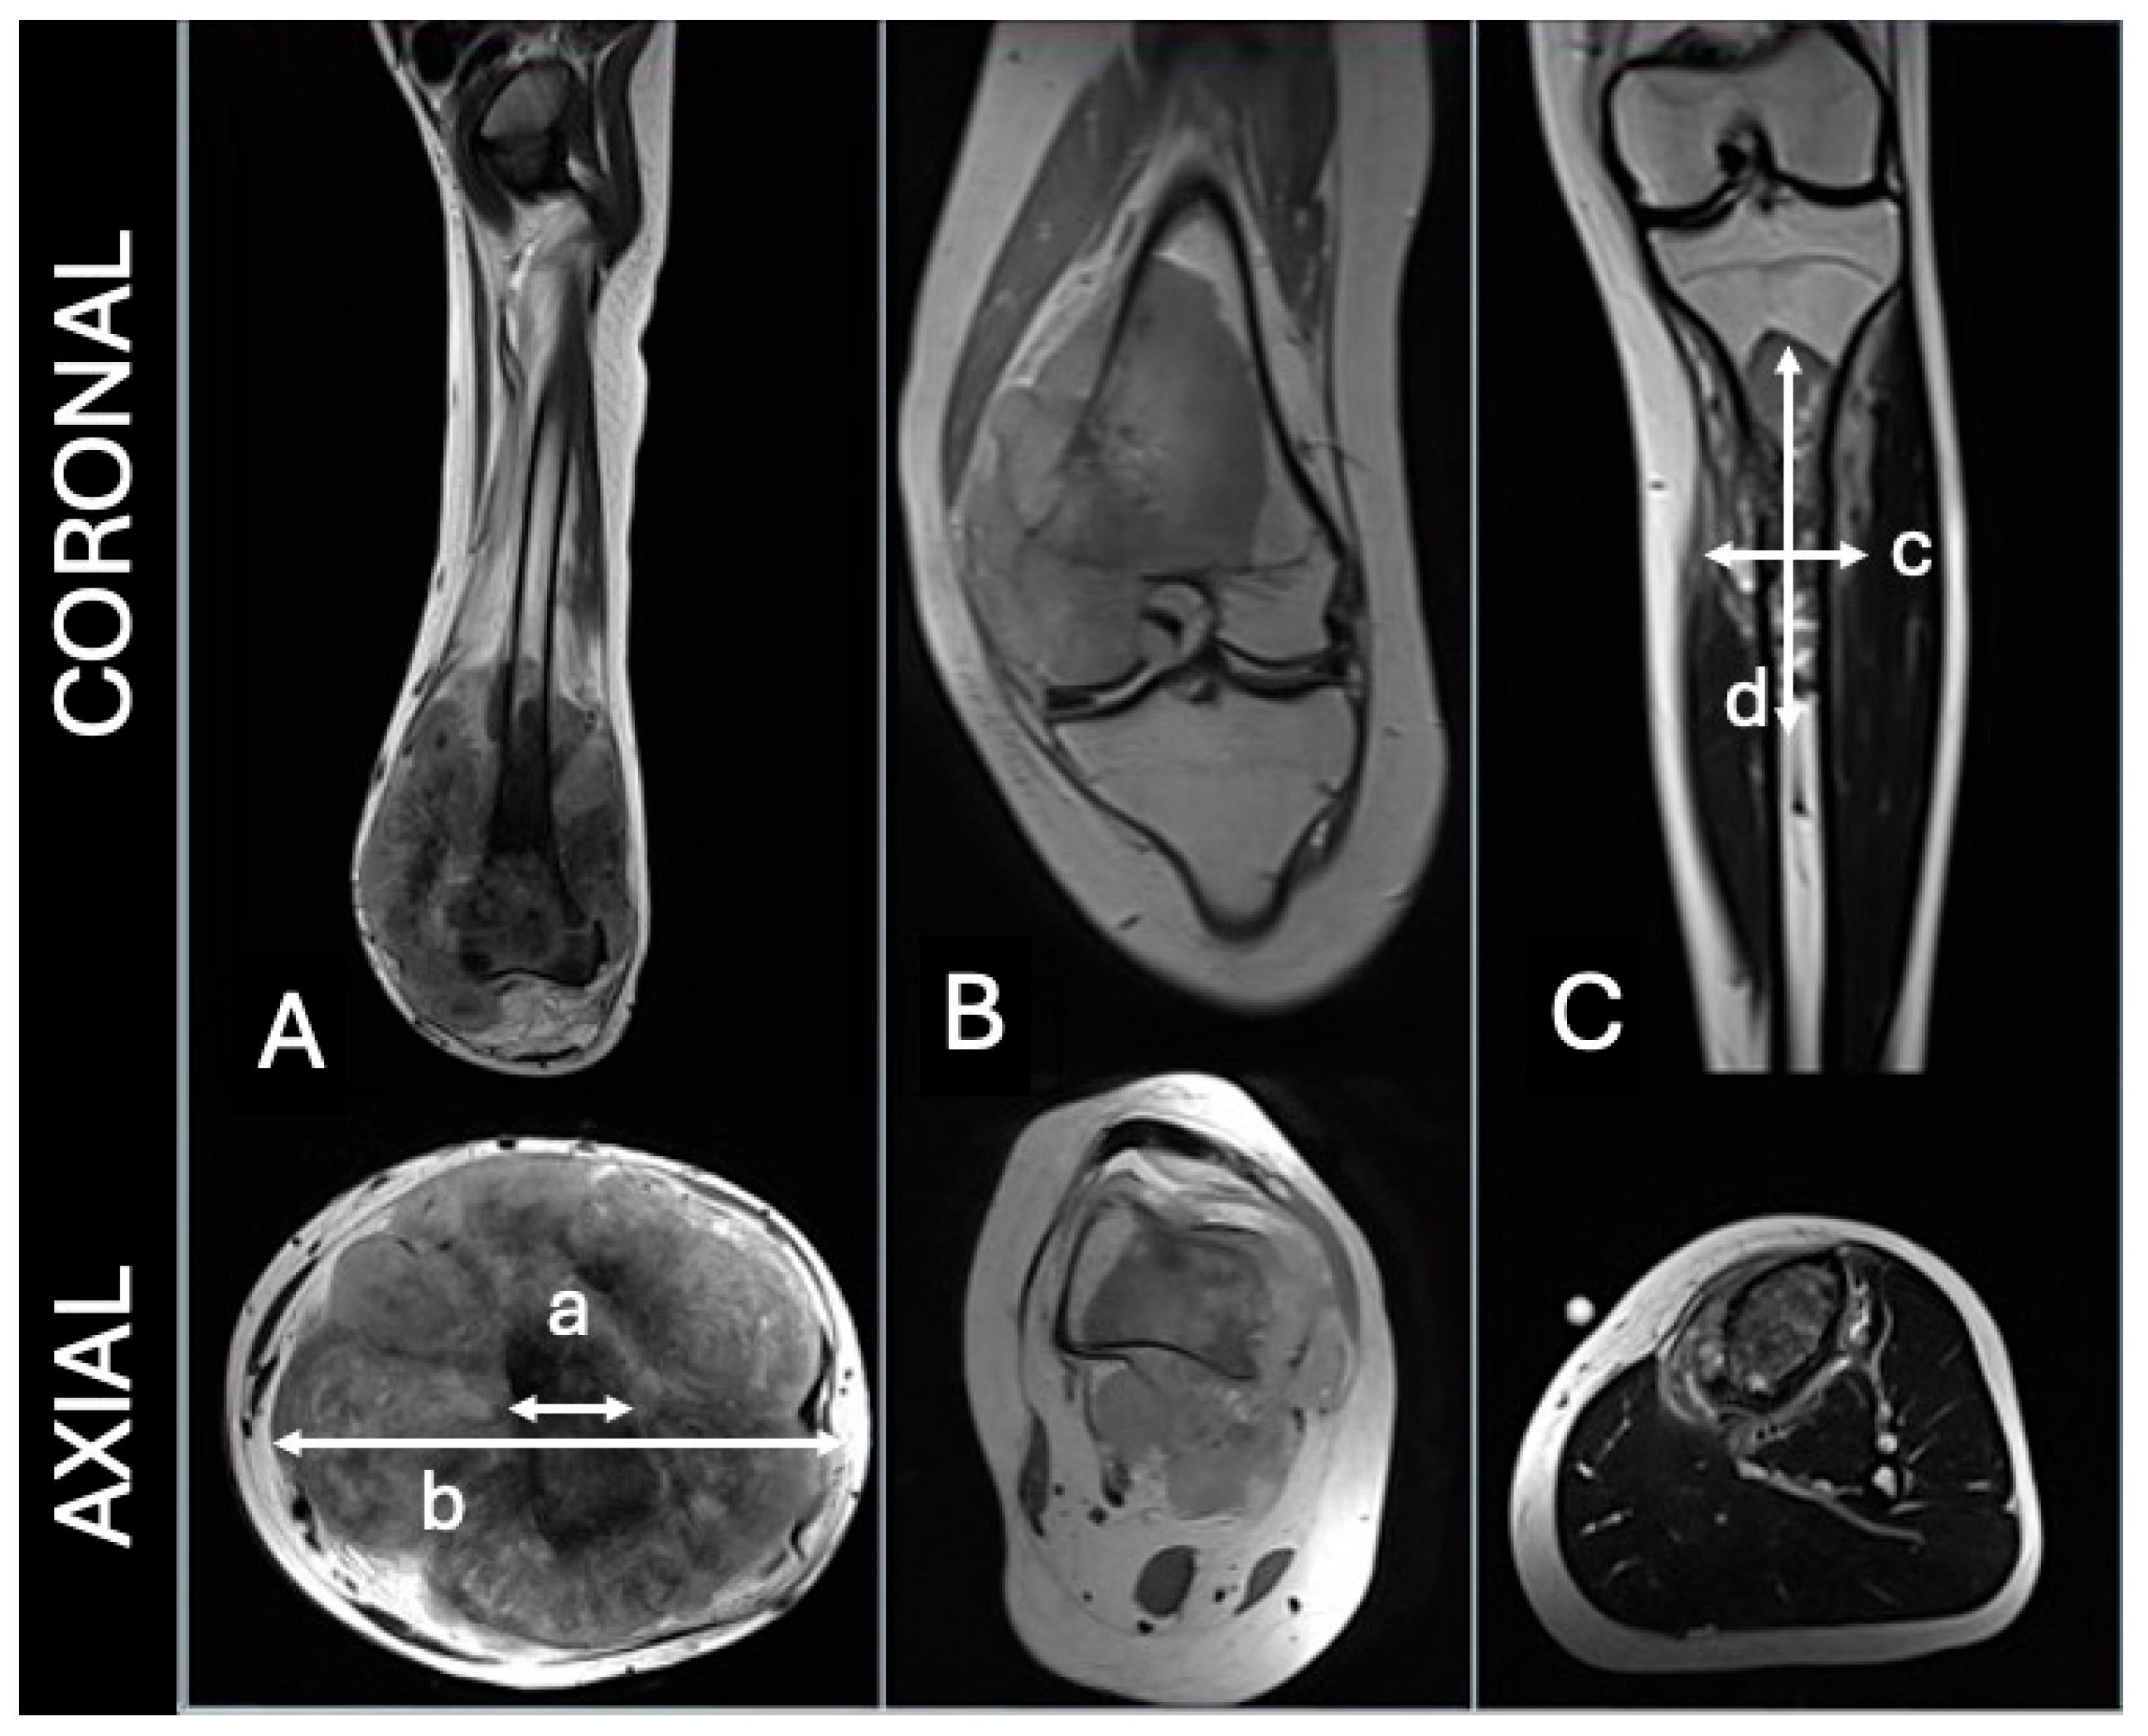

2.2. Analysis and Definition of Study Variable